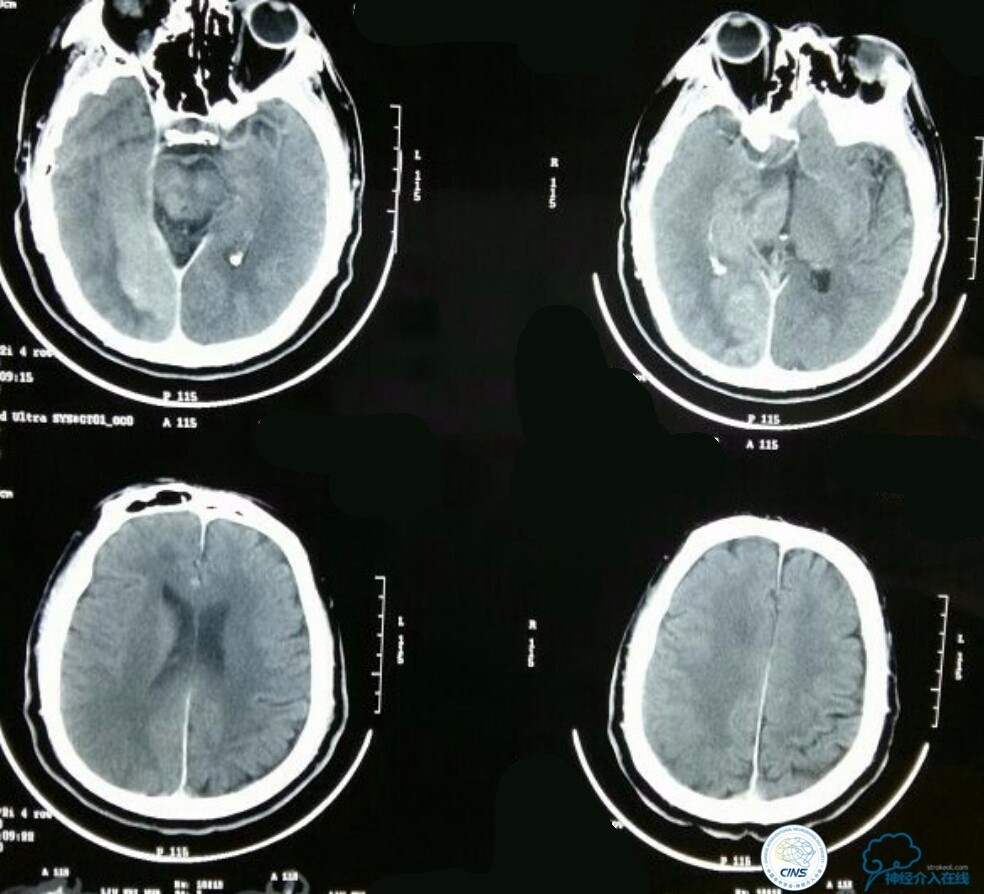

查体:浅昏迷,双侧瞳孔不等大,D右:D左=3.0:1.5mm,对光反射消失,左侧鼻唇沟变浅,左眼闭合不全,左侧肢体肌力0级,左侧病理症(+),其余查体不能配合,内科查体无异常。NIHSS评分:20分,心电图:正常心电图,随机血糖:17mmol/l,头颅CT:未见异常。

术后生命体征平稳,成功撤呼吸机,肌力较前好转,复查头颅CT:

右侧丘脑高密度影,右侧枕叶可能也有梗死,祈祷慢慢恢复吧!